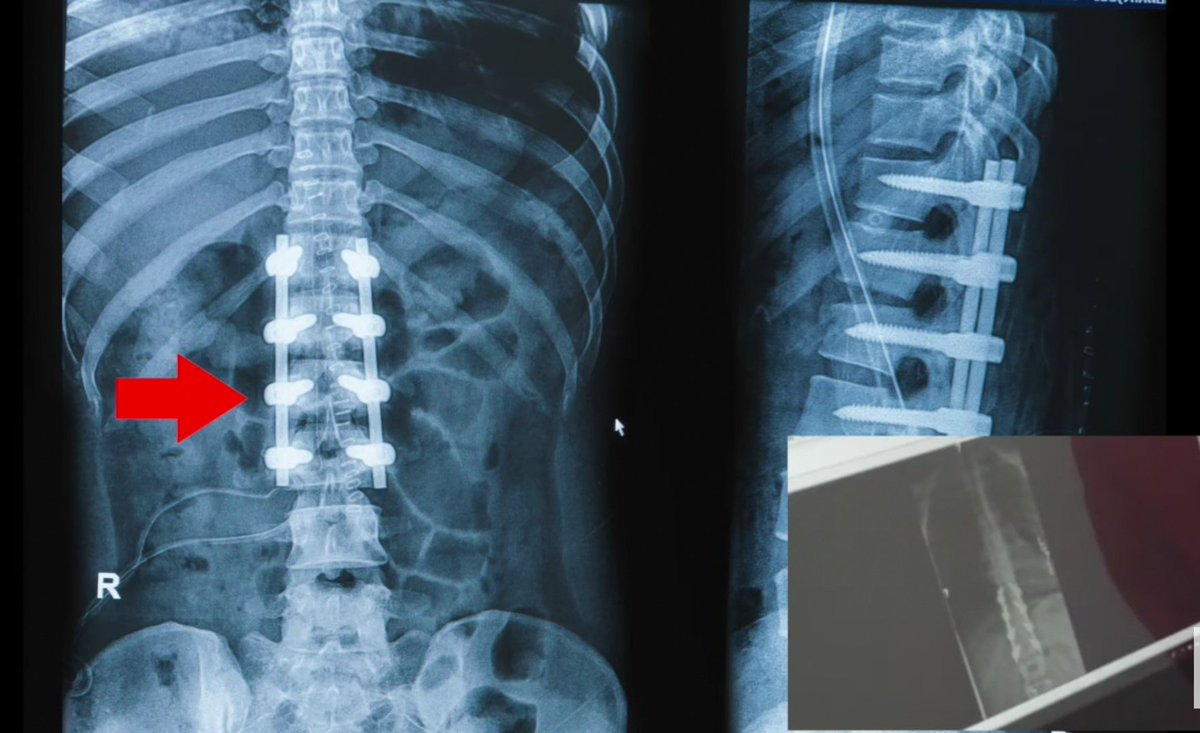

كان عبارة عن دمج 3 كسور في العمود الفقري كما هو موضح

ـ بالـ MRI?

⁦⤵️⁩